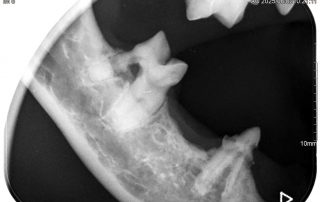

Werden die Zähne nicht täglich intensiv geputzt, bleibt ein Belag, die „Plaque“ zurück. In diese Schicht lagern sich nach und nach Mineralstoffe und Bakterien ein. So entsteht an den Außenflächen der Zähne harter, braungrauer Zahnstein. Durch die Eiter erregenden Keime in Plaque und Zahnstein entzündet sich das Zahnfleisch, es wird rot und riecht Übelkeit erregend. Schreitet die Zahnfleischentzündung (Gingivitis) weiter voran, verlieren die Zähne oft vollständig ihren Halt, bleiben aber als ständiger Entzündungsherd häufig noch jahrelang im Kiefer. Häufig entstehen, vielfach unterhalb des Zahnfleischsaumes, Löcher in den Zahnhälsen und Zahnwurzeln. Diese werden als FORL (feline odontoklastische resorptive Läsionen) bezeichnet; Die Zahnsubstanz löst sich regelrecht auf.

Zunächst ist die Entfernung des krank machenden Zahnsteins und die Wiederherstellung eines gesünderen Zahnfleisches wichtig. Da die Beläge auf den Zähnen mit einem Ultraschallgerät entfernt und die Zähne anschließend aufwändig poliert werden müssen, ist eine schonende altersangepasste Vollnarkose unumgänglich. Lockere und bereits angegriffene Zähne werden entfernt. Wegen der Eiterbakterien werden Antibiotika über eine bestimmte Zeit ebenso verabreicht wie wirkungsvolle Schmerzmedikamente.

Um ihren Tieren eine noch bessere zahnmedizinische Versorgung anzubieten, haben wir uns im vergangenen Jahr eine sehr hochwertige Dentaleinheit (Profident Plus) der Firma Eickemeyer gekauft. Damit können wir nun problemlos festsitzende mehrwurzlige oder auch abgebrochene Zähne spalten bzw. entfernen.